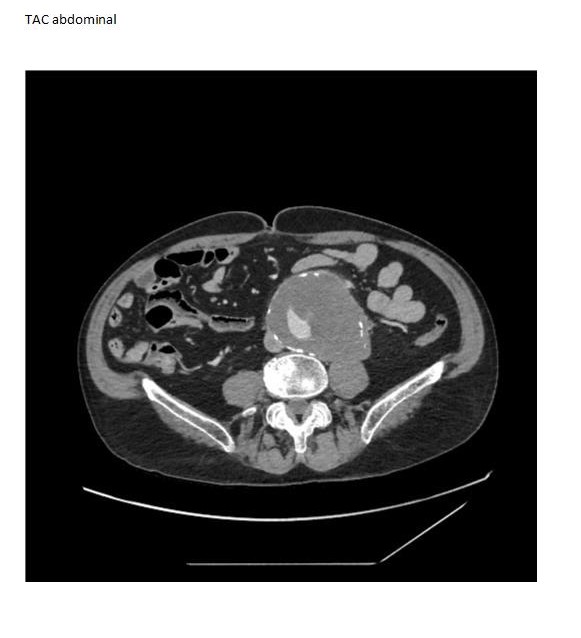

TAC abdominopevico: Aneurisma aorta abdominal (AAA) infrarrenal. Se observan signos de inestabilidad/rotura inminente, diámetro de 10 cm.